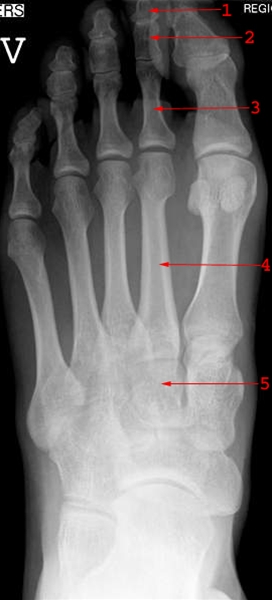

Røntgenbillede af fod set fra oven

Foden består totalt af 26 knogler. På billedet ses: 1) yderstykke af 2. tå. 2) mellemstykke af 2. tå. 3) grundstykke af 2. tå. 4) mellemfodsknogle (metatars). 5) kileben (cuneiforme intermedia).